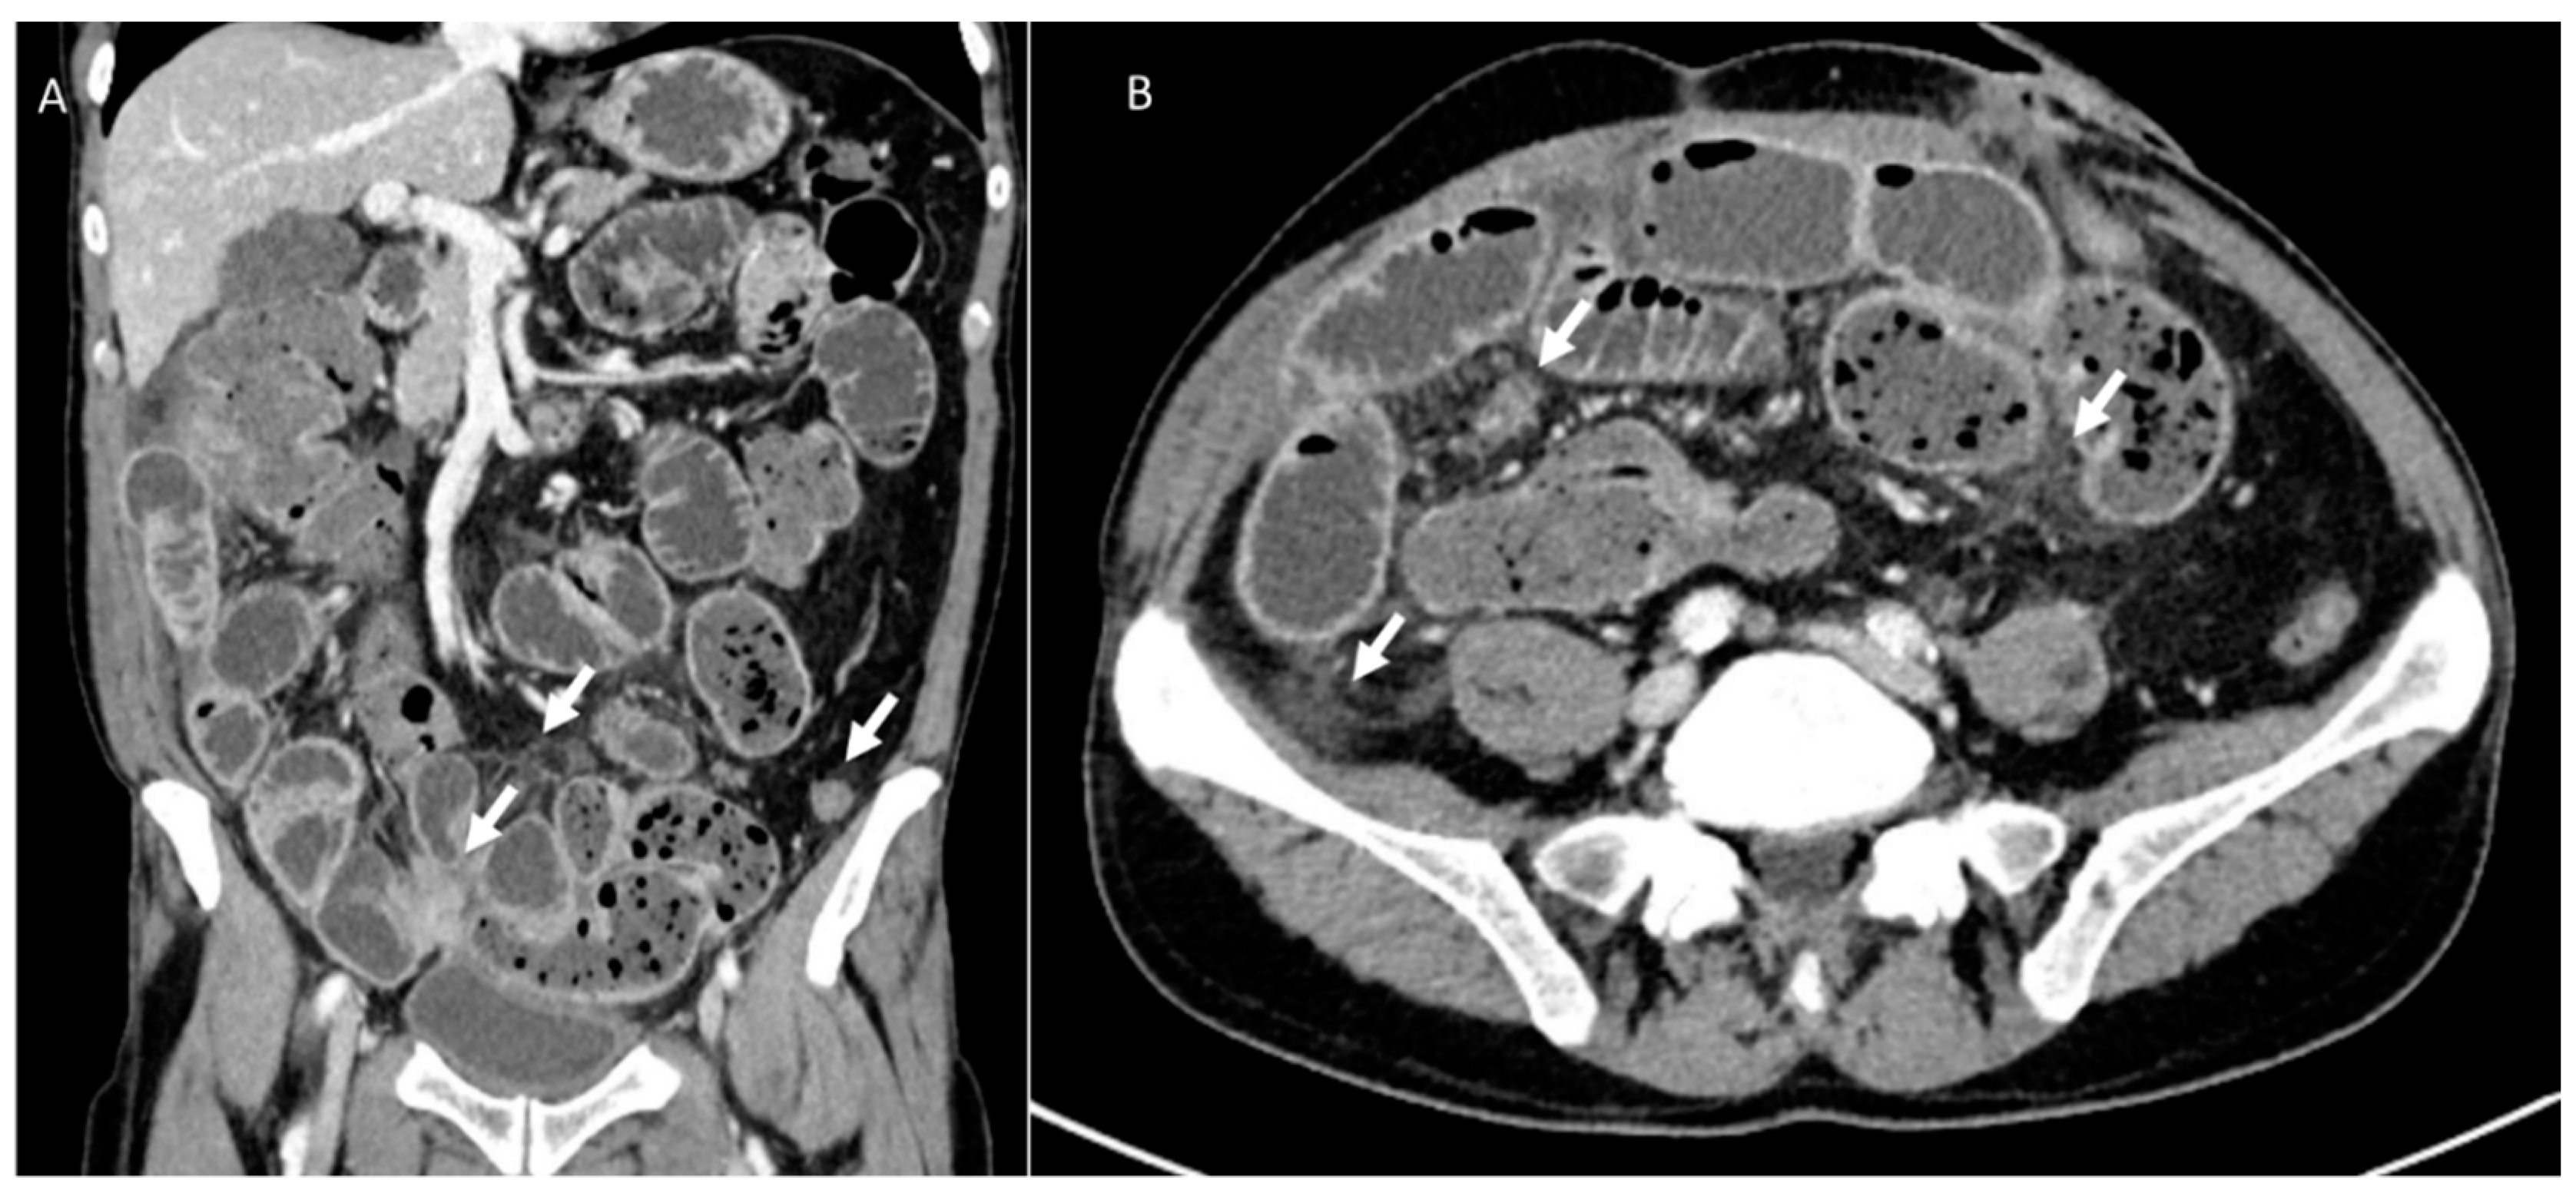

3.6. Hernia

3.7. Local Recurrence